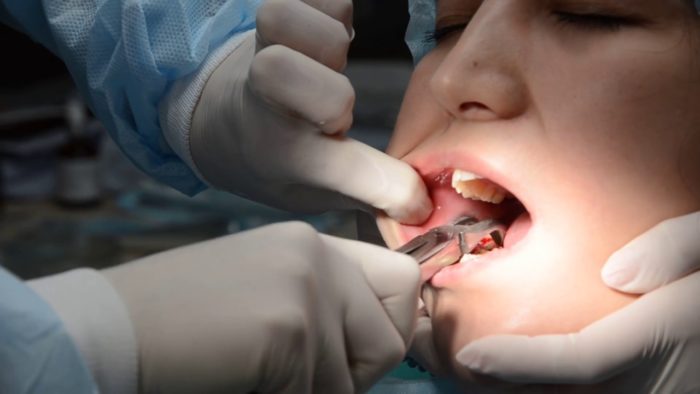

Процесс удаления

Тактика удаления зуба при флюсе определяется во время диагностики. Далее пациенту ставят обезболивающие уколы в необходимом количестве. Одна из методик удаления выглядит так:

Очень важно соблюдать санитарные нормы, чтобы не допустить повторного заражения тканей или крови.